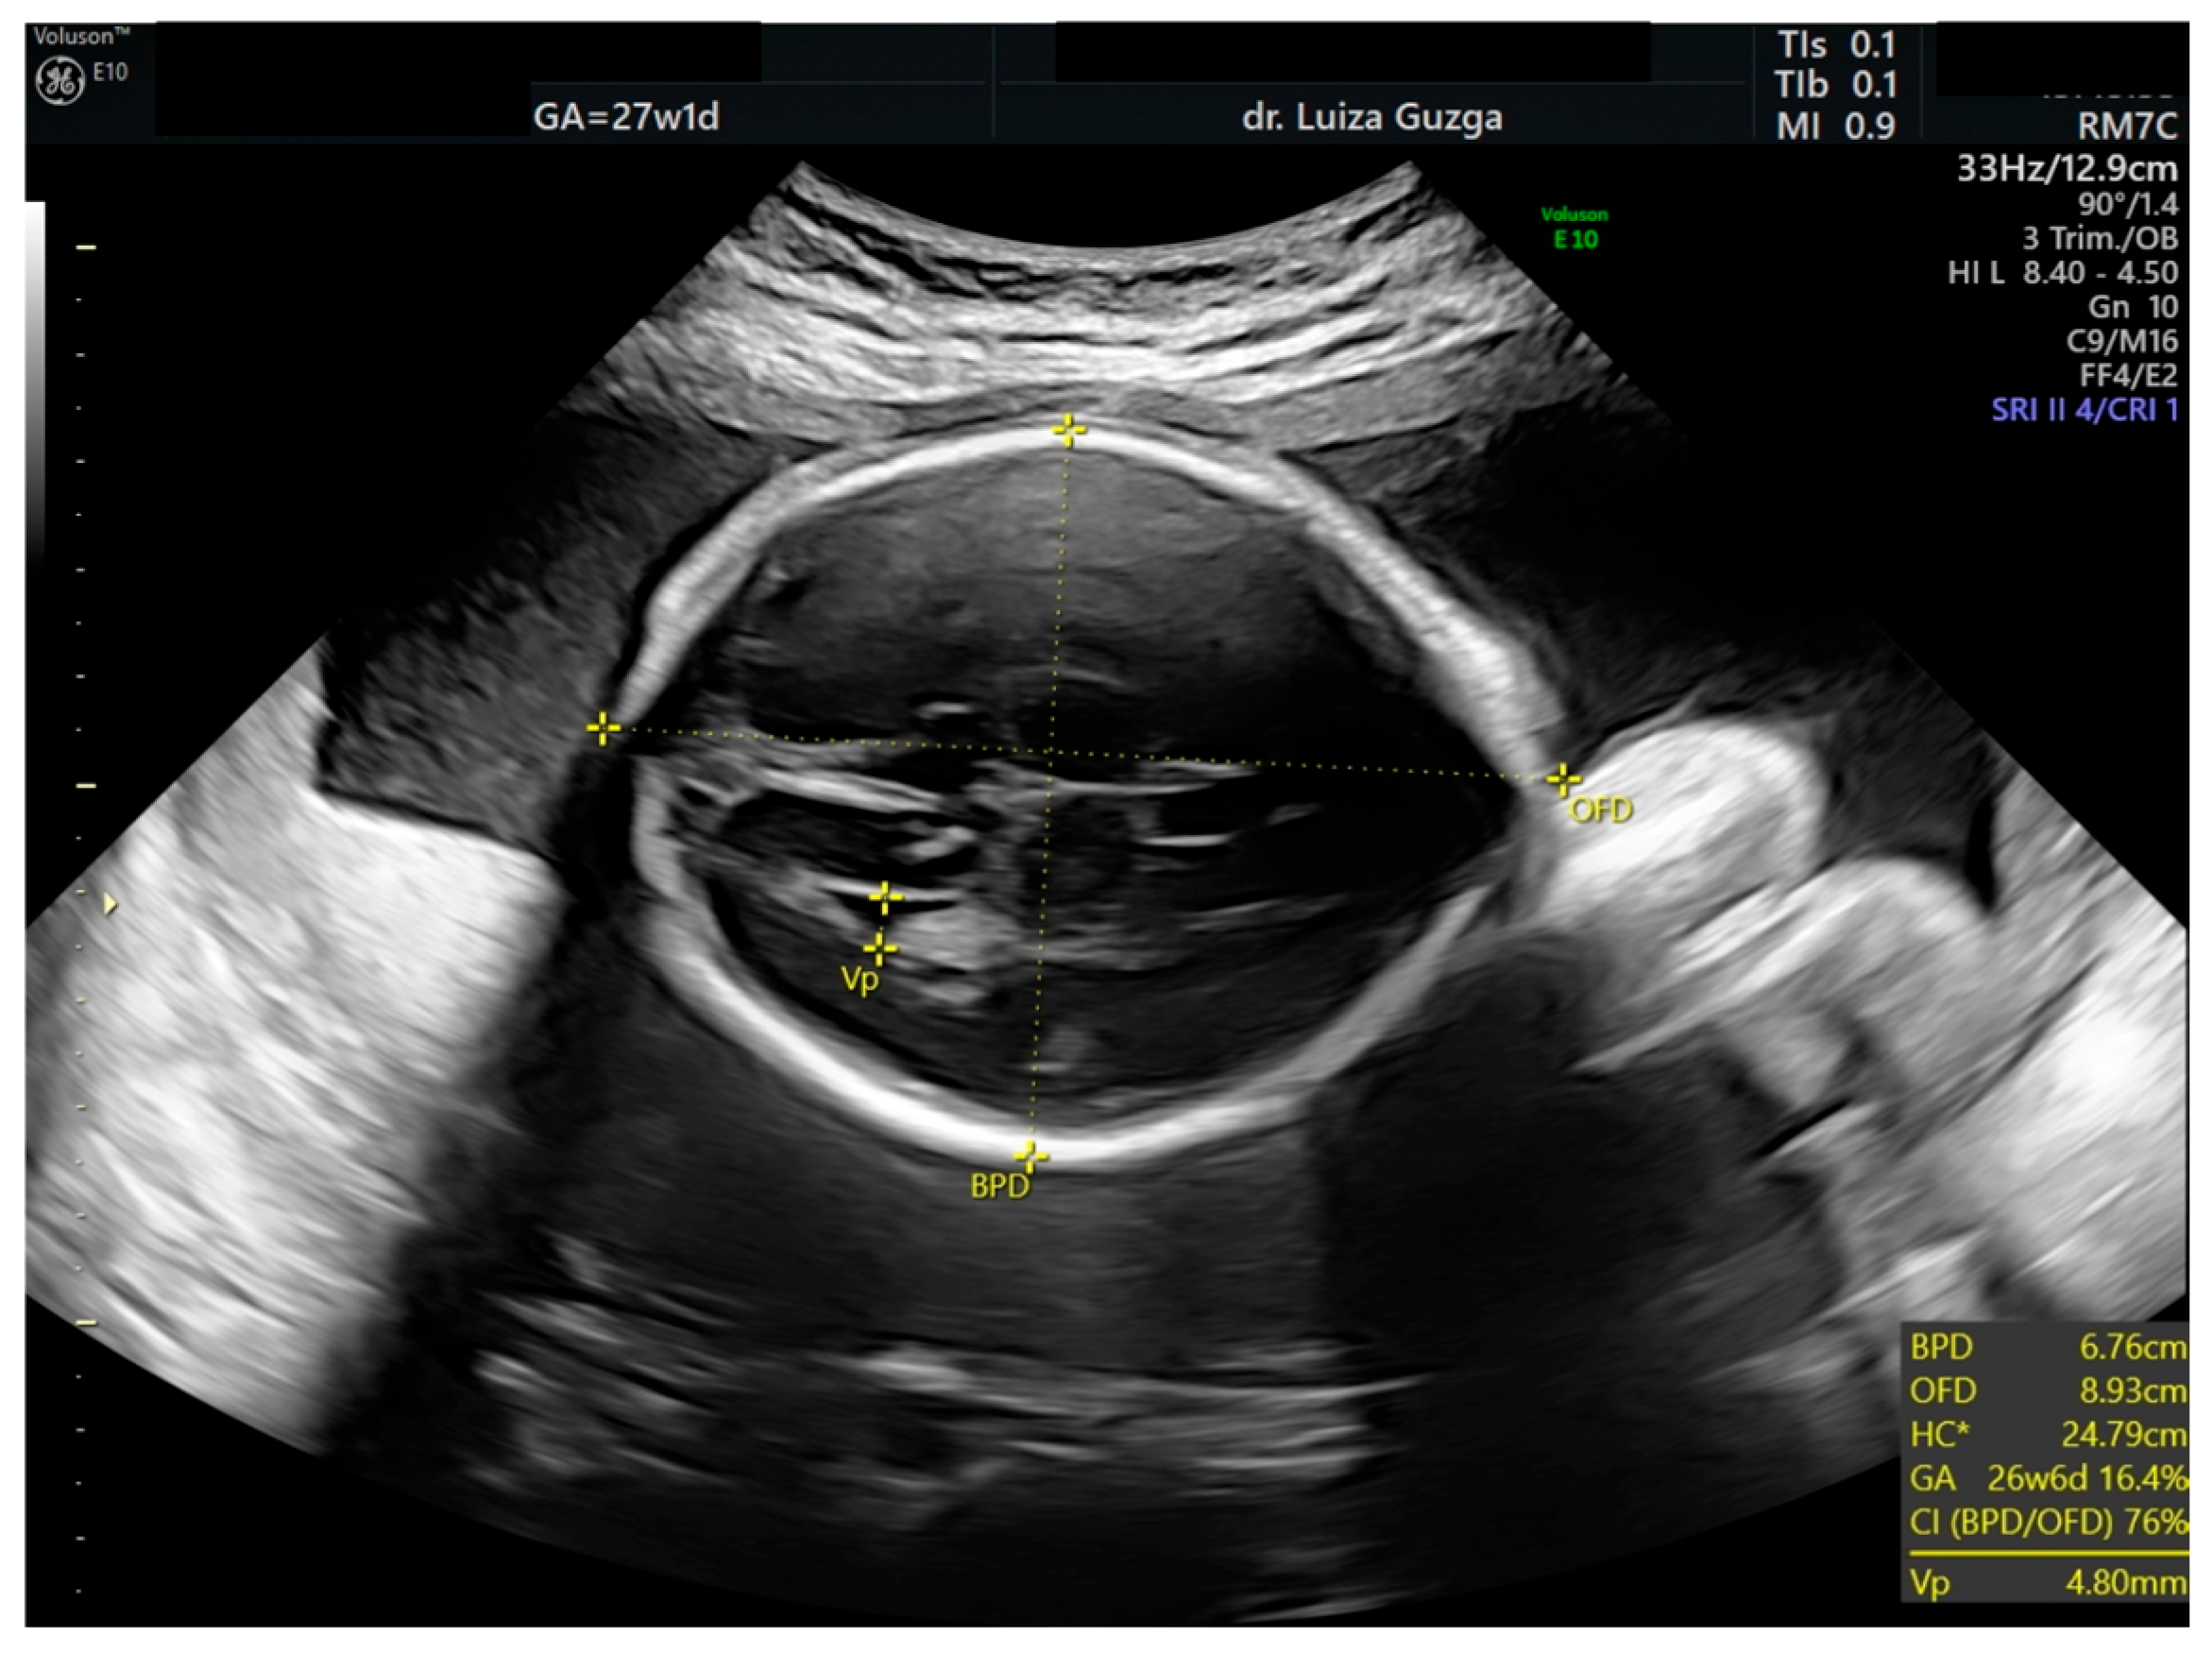

2.1. Case Presentation

2.2. Case Management

| Prenatal Ultrasound Findings | 21 + 6 | 26 + 6 | 28 + 6 | Frequency of Postnatal Findings in the Literature |

| Pointed forehead/premature closure of the metopic suture | - | + | +++ | ? |

| Hypotelorism | - | + | +++ | Rather hypertelorism |

| Micrognathia/small chin size | - | + | +++ | +++ |

| Corpus callosum hypoplasia | - 19.9 mm > 5% (19.54 mm) | + 27.7 mm < 5% (29.91 mm = 5%) | Difficult to visualize—premature metopic suture closure | ++ |

| Broad thumb | - | +++ | +++ | +++ |

| Rocker-bottom feet | - | +++ | +++ | +++ |

| Short femur | - | + | ++ | +++ |

| Low-lying conus medullaris | - | + | + | + |

| Increased pulmonary valve echogenicity with normal PSV | - | + | + | ++ |

| Bilateral cryptorchidism Shawl scrotum with excessive rugae | - | ++ | ++ | ++ |